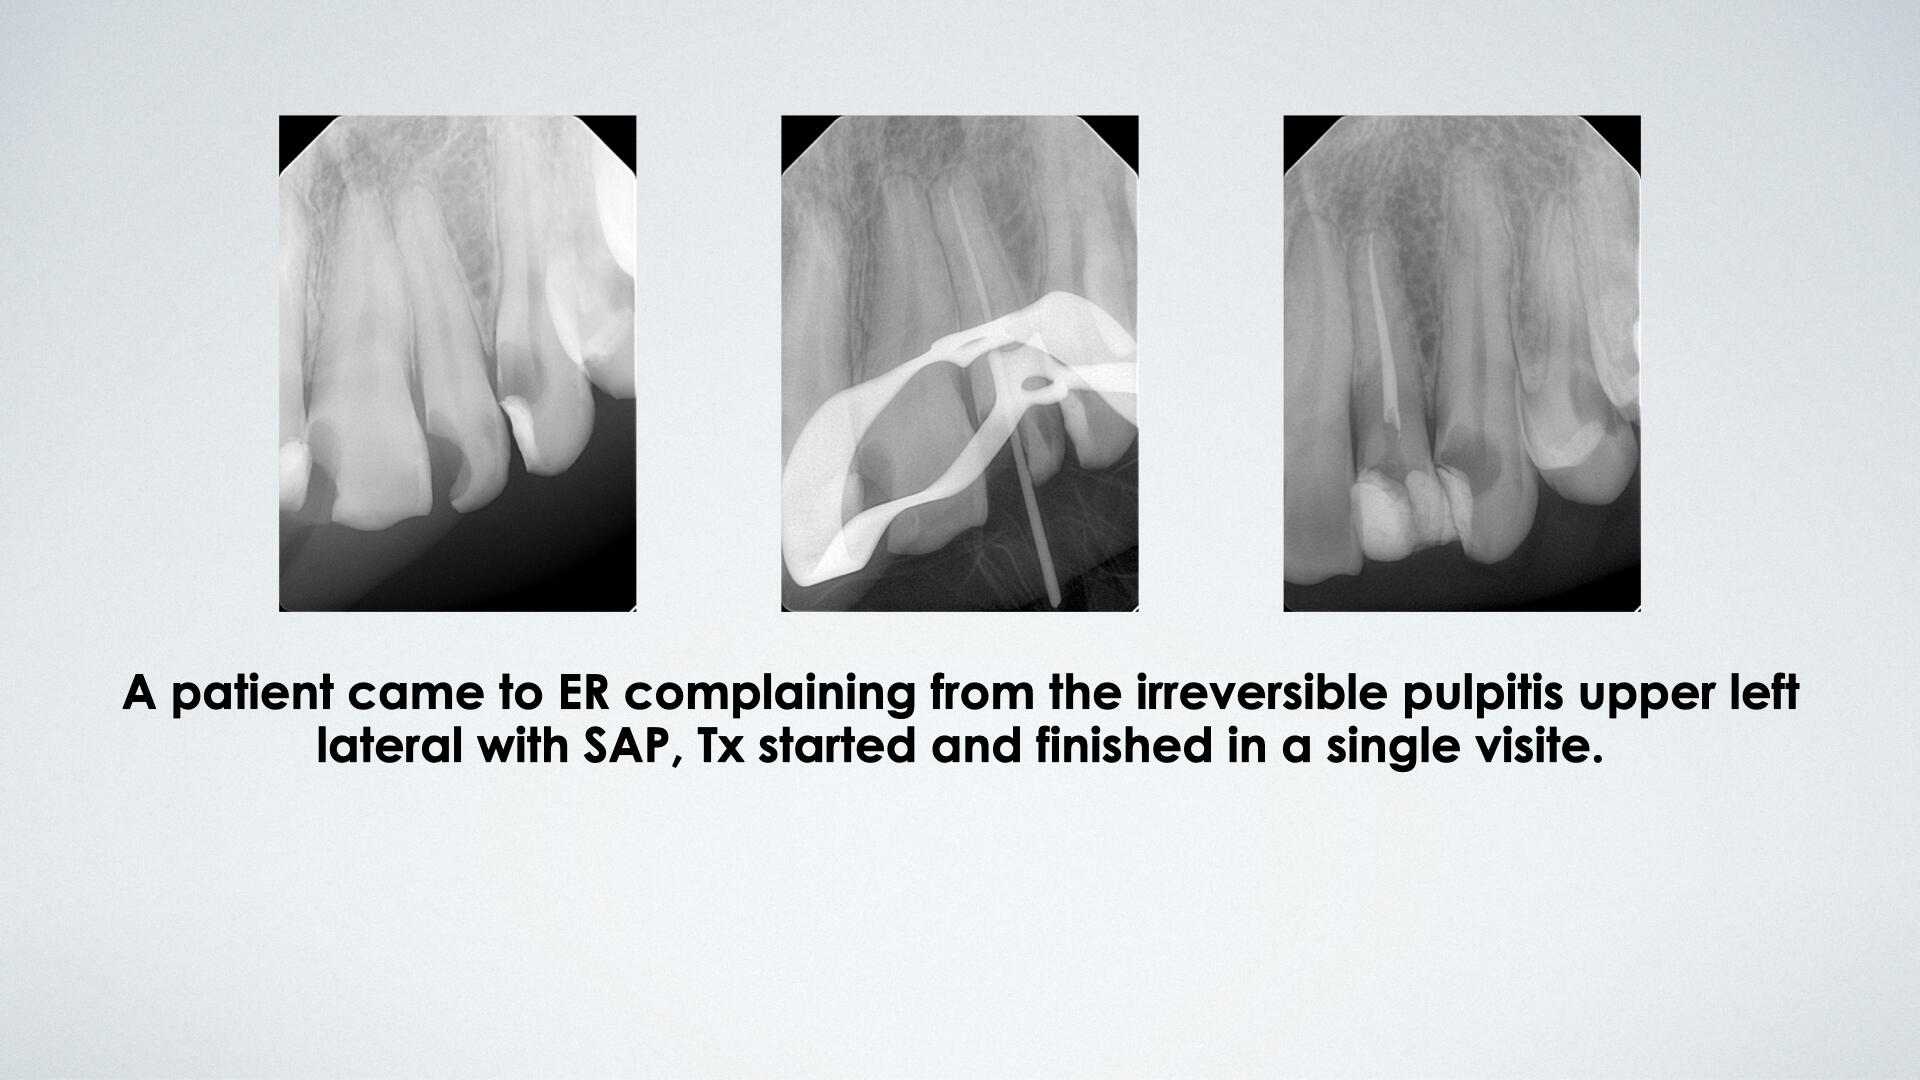

During my internship term, I have worked on 400+ different patients with a variety of cases. Portfolio includes esthetic, direct restoration, RCT and prothodintic cases.